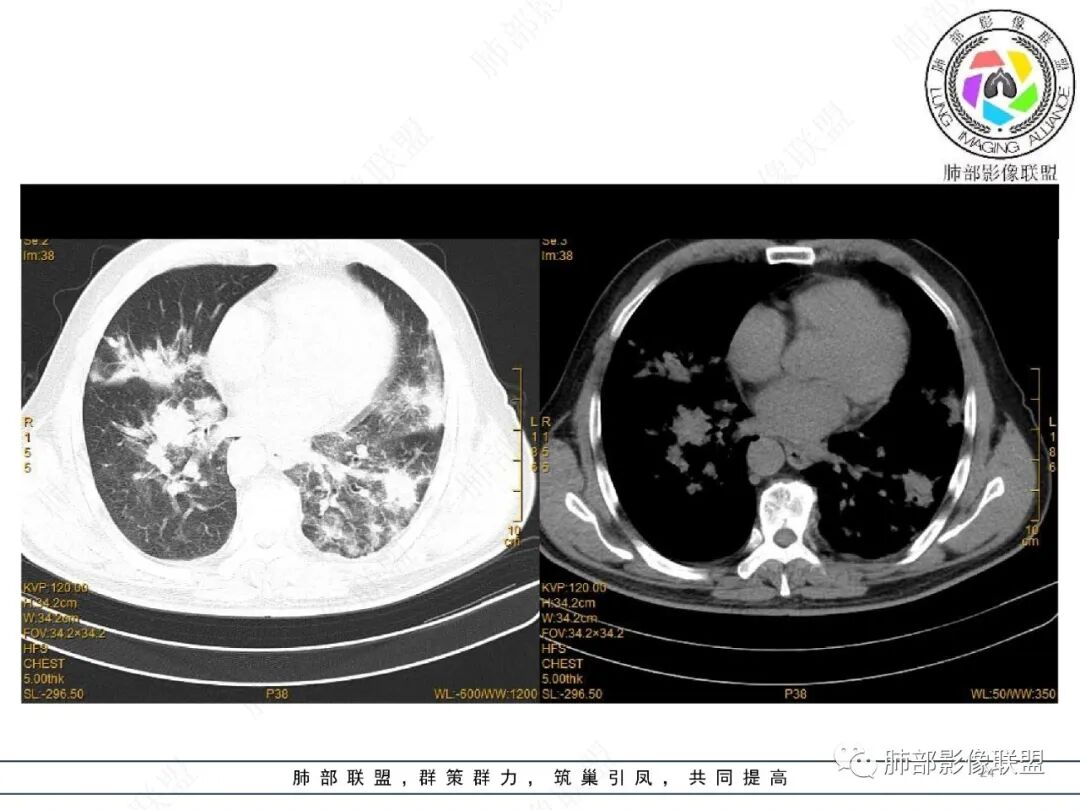

2022.2.17CT显示两肺中内带多发结节影、斑片影、条索影,部分病灶侧向融合与胸膜平行。部分病灶沿着支气管血管束分布、其内支气管稍扩张。部分病灶呈反晕征。大部分病灶边界显示清晰,部分病灶周围可见边界不清的GGO。2022.4.12CT显示两肺中内带多发结节影、条索状、条带状高密度影,边界收缩平直凹陷,大部分病灶沿着支气管血管束分布,亦有位于胸膜下侧向融合与胸膜平行的病灶。总体与第一次CT对比两肺病灶明显吸收。